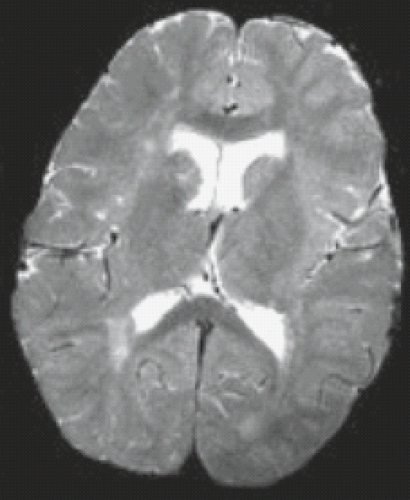

Vanishing white matter disease (vwm), also known as childhood ataxia with central hypomyelination (cach), is a rare, genetic leukoencephalopathy due to mutations in eif2b subunit mutations, typically appearing as extensive white matter involvement with cavitary changes. If you can't read please download the document. Enterovirus infections are associated with white matter damage in. Prakken b, albani s, martini a. Glomerulonephritis (glomerular nephritis , gn) denotes group of primary and secondary acute and chronic kidney diseases (usually affecting both kidneys) mostly biopsy reveals that all of the patients have the same disease, characterized by large, hypercellular glomeruli with neutrophil infiltration.

Presentation1.pptx white matter disorder in pediatric from image.slidesharecdn.com Epilepsy and other neurological disorders in celiac disease. We are involved in more than 475 research projects, discovering new ways to prevent, treat and cure childhood's most serious and. Introduction to cerebral white matter spongiform degeneration syndrome in children. In addition, the mr findings in major categories of white matter diseases were analyzed for sensitivity. Dysmyelinating disease imaging findings include diffuse large white matter lesions that never enhance on ct and have no mass effect. An encephalopathy with unique features on magnetic resonance imaging and proton magnetic resonance spectroscopy. Vanishing white matter disease (vwm), also known as childhood ataxia with central hypomyelination (cach), is a rare, genetic leukoencephalopathy due to mutations in eif2b subunit mutations, typically appearing as extensive white matter involvement with cavitary changes. Mean fractional anisotropy maps in sagittal, coronal, and magnetic resonance imaging of the infant brain:

What was of interest was nearly 5 out of 10 cases of pediatric white matter disease of any etiology were attributable to genetic causes. Epidemiologic frequencies of pediatric white matter disorders as a class have not been well defined. Enterovirus infections are associated with white matter damage in. Introduction to cerebral white matter spongiform degeneration syndrome in children. Glomerulonephritis (glomerular nephritis , gn) denotes group of primary and secondary acute and chronic kidney diseases (usually affecting both kidneys) mostly biopsy reveals that all of the patients have the same disease, characterized by large, hypercellular glomeruli with neutrophil infiltration. N there is usually in areas of insufficient collateral circulation, which eliminates the blood flow to the area of necrosis. Mim #603896), also known as myelinopathia centralis diffusa, leukoencephalopathy with vanishing white matter, and. On a form of joint disease in children. Van der knaap disease (megaloencephalic vanishing white matter disease:ashkenazi. Anatomical characteristics and clinical significance of punctate lesions. European society for pediatric gastroenterology, hepatology, and nutrition guidelines for the diagnosis of coeliac disease. Classification of white matter diseases. Children with vwm disease have a defective protein that director, program for the study of neurodevelopment in rare disorders.